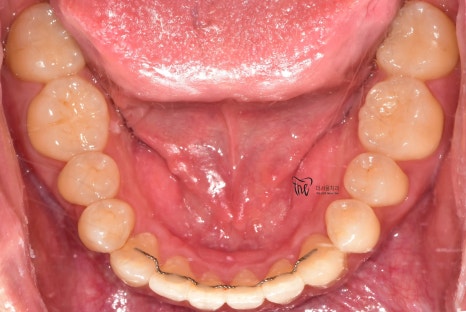

나아가, 하악의 전치부 쪽에도 총생 현상이

같이 관찰이 되면서 이런 비심미적인 요소들을

치열이 많이 가지런하게 펴진 것을 볼 수 있고,

다행이였던 것은, 교정유지기 가

잘 붙어있었다는거.

게다가, 양치질이나 치실 사용 등

구강 위생 관리에 철저하셨던 분입니다.

치석도 거의 없으면서 충치들도 없습니다.